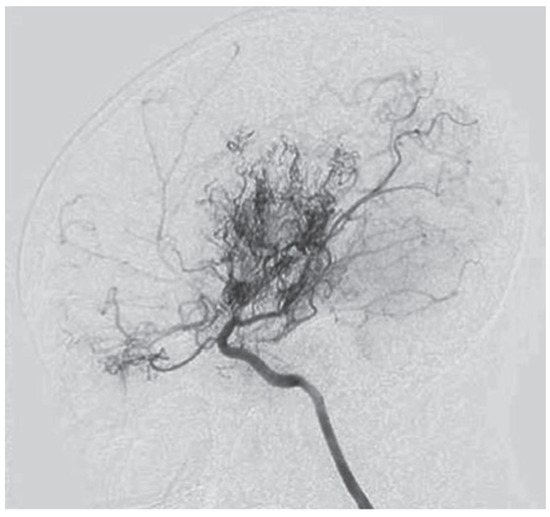

An MRI of the head (Figure 3) showed multiple long-standing ischemic lesions in all regions of the cerebral vasculature and significantly reduced blood flow in all arteries of the anterior circulation (Figure 4). Doppler ultrasonography of the extracranial vessels did not show any abnormalities. EEG revealed marked interhemispheric asymmetry—diffusely slowed, not well-organized brain activity in the right hemisphere, and in the left, not well-organized alpha rhythm with frequent single or multiple temporoparietal spikes. Abdominal ultrasound, consultation with a vascular surgeon, duplex ultrasonography of the lower limb vessels, consultation with a cardiologist, ECG, and echocardiography were all unremarkable for any pathology. Computed perimetry for the evaluation of visual field defects could not be accomplished due to excessive myopia, reduced visual acuity (20/800), and cognitive impairment. The serum level of valproate was 61.68 μg/mL.

Figure 4. MRI time-of-flight (TOF) angiography showing significantly diminished blood flow in the anterior circulation and the development of collateral blood vessels.